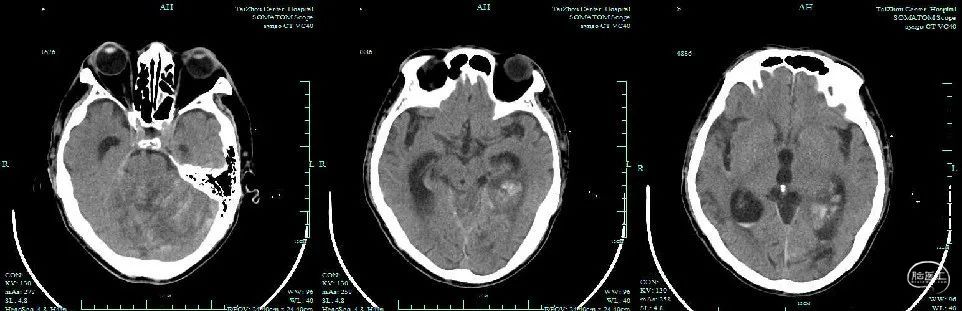

引流术后头颅CT

出院:意识清楚,查体欠配合,右上肢肌力III级,右下肢肌力II级,双侧巴氏征阴性。房颤心律。